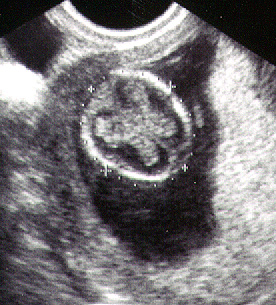

توأمان في الاسبوع الخامس

يبدأ الجنين في الأسبوع الخامس في بداية تكوينه ويسمى في هذه الفترة وحتى 3 شهور (حميل) والحميل هو الجنين منذ بداية تلقيح البويضة وحتى الأسبوع 12. فهو الآن ينمو داخل الرحم. وينقسم إلي ثلاث طبقات تكون كل طبقة منهم الأعضاء والأنسجة فيما بعد. وفي مؤخرة الرأس لأسفل، هناك طبقتين نسيج تكون الأذن بعد ذلك.

أما عن الأنبوب الذي تكون في الظهر في الأسبوع الرابع والذي تحدثنا عنه سابقاً والذي يخرج منه المخ، العمود الفقري، الأعصاب وتنشق منه أيضاً عظمة الظهر يبدأ في النمو في الطبقة العلوية للظهر. أما بالنسبة للقلب فهو يبدأ في الظهور في الطبقة الوسطى. والطبقة الثالثة فهي تحتوي علي الرئة، المعدة، وبداية الجهاز البولي. في نفس الوقت فإن الشكل الأولي للمشيمة والحبل السري الذي يقوم بنقل الغذاء إلي الجنين يكونان في الطور الأولي لبداية وظائفهما. إذا لم تكوني قمت بإجراء اختبار حمل منزلي حتى الآن فيجب القيام به وإذا تم التأكد من الحمل، فيجب اللجوء للطبيب المتخصص لاستشارته في الحالة.